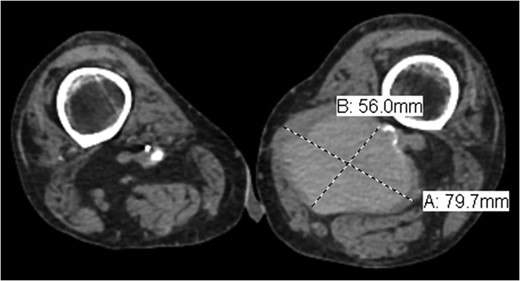

Pseudoaneurysm (PA) following vascular reconstruction is a complication of bypass surgery. Historically, the mainstay of treatment was an open repair; the surgical management consisted of resection of the initial graft with reimplantation of a new bypass either into the original arteriotomy or to a more distal target. Placement of a stent graft to exclude the PA is a viable option. We present a case of an 85-year-old man with prior history of polytetrafluoroethylene femoral–popliteal bypass now with an 8 × 5.6 cm PA of the distal anastomosis site treated with endovascular placement of a Viabahn stent.

Pseudoaneurysm (PA) formation has been described in the literature as a delayed presentation in surgically revascularized patients. Given the rising number of reconstructive vascular procedures, the increase in anastomotic PA cases is expected [1]. Potential degeneration of biosynthetic grafts with aneurysm formation is a well-known problem with a reported incidence of up to 7% [2]. Implantation of a stent graft for treatment of a PA is a valuable treatment option in native arteries, as well as bypass grafts, as reported by Magnetti et al. [2]. In high-surgical-risk patients, the placement of a stent graft provides a safe and effective option for the treatment of anastomotic PA. We present a case of an 85-year-old man with prior history of polytetrafluoroethylene (PTFE) femoral–popliteal bypass now with an 8 × 5.6 cm PA of the distal anastomosis site treated with endovascular placement of a Viabahn stent. Of note, the patient underwent open thrombectomy and patch angioplasty of the site 10 years prior. Proper written consent was obtained from the patient prior to the creation of this case report.

Coronal view of popliteal PS of distal anastomosis site of femoral–popliteal bypass.